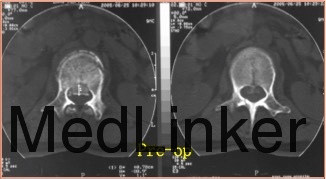

查体:卧床状态,腰部活动不能,行走不能,腰2棘突上叩痛,压痛(+)。双下肢大腿中段以下皮肤感觉减退、肌力正常,膝反射及膝踝反射正常,双侧Babinski征(-)。 辅助检查:CT检查示腰2椎体爆裂性骨折。椎管内占位改变。

诊断:腰2椎体爆裂性骨折(AO分型:A3.1) 治疗:给予急诊行腰1-腰2椎弓根钉固定+骨折复位术。术中行椎板切除减压,用骨冲将突入椎管的骨块复位。